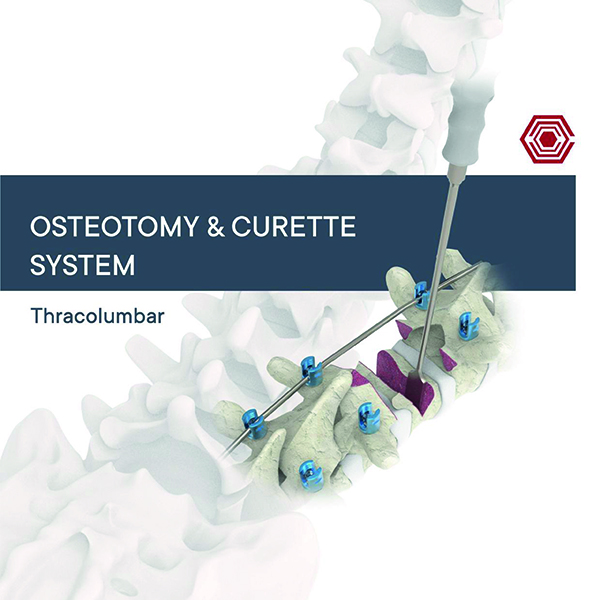

Osteotomy & Curette System

Akif Kaya Aybek

Norm Akademi

- Surgical Technique

- Instrument Container

- Instrument Types